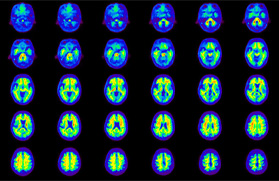

Head / Case4 : Amyloid

Axial

Courtesy : Kindai University Hospital

- Imaging protocol

- Injected dose: 3.21 MBq/kg, 18F-Flutemetamol

- Uptake time: 100 minutes

- Scan time: 20 minutes